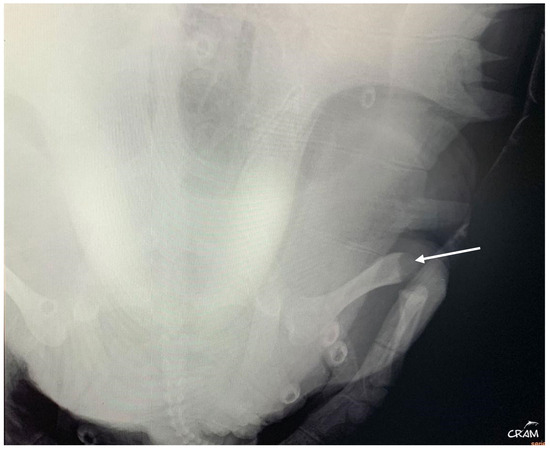

Visible swelling and lameness of the right fore and hind flippers were first noted around day 45 of rehabilitation (Figure 4). The turtle had reduced use and range of motion of the affected limbs. Palpation of right elbow and right knee elicited a pain response. Both joints presented increased periarticular soft tissue. A radiographic study of the turtle was performed and showed poorly defined osteolytic process restricted to the distal end of the humerus and femur and the proximal end of the radius and tibia. In the case of DON, changes in imaging are seen early at 4 months after hyperbaric exposure and can be seen as late as 8 months to more than a year [6]. Radiographic studies were repeated every 10–14 days to evaluate the progression of the lesions.

Therefore, to better visualize the lesions, computed tomography (CT) of the whole body, in soft tissue and bone algorithm, with 1.25 mm thick sections, without administration of intravenous iodinated contrast, was performed. CT confirmed the lytic lesions observed in radiography on the distal right humerus, proximal right radius and ulna, distal right femur, and proximal right tibia and fibula. When clinical signs appeared, blood culture at 24–26 °C with antibiogram was performed, revealing a positive result.

Figure 6. Right pelvic girdle in dorso-ventral view at day 45 of rehabilitation. Visible bone lysis on the distal end of the right femur (arrow).